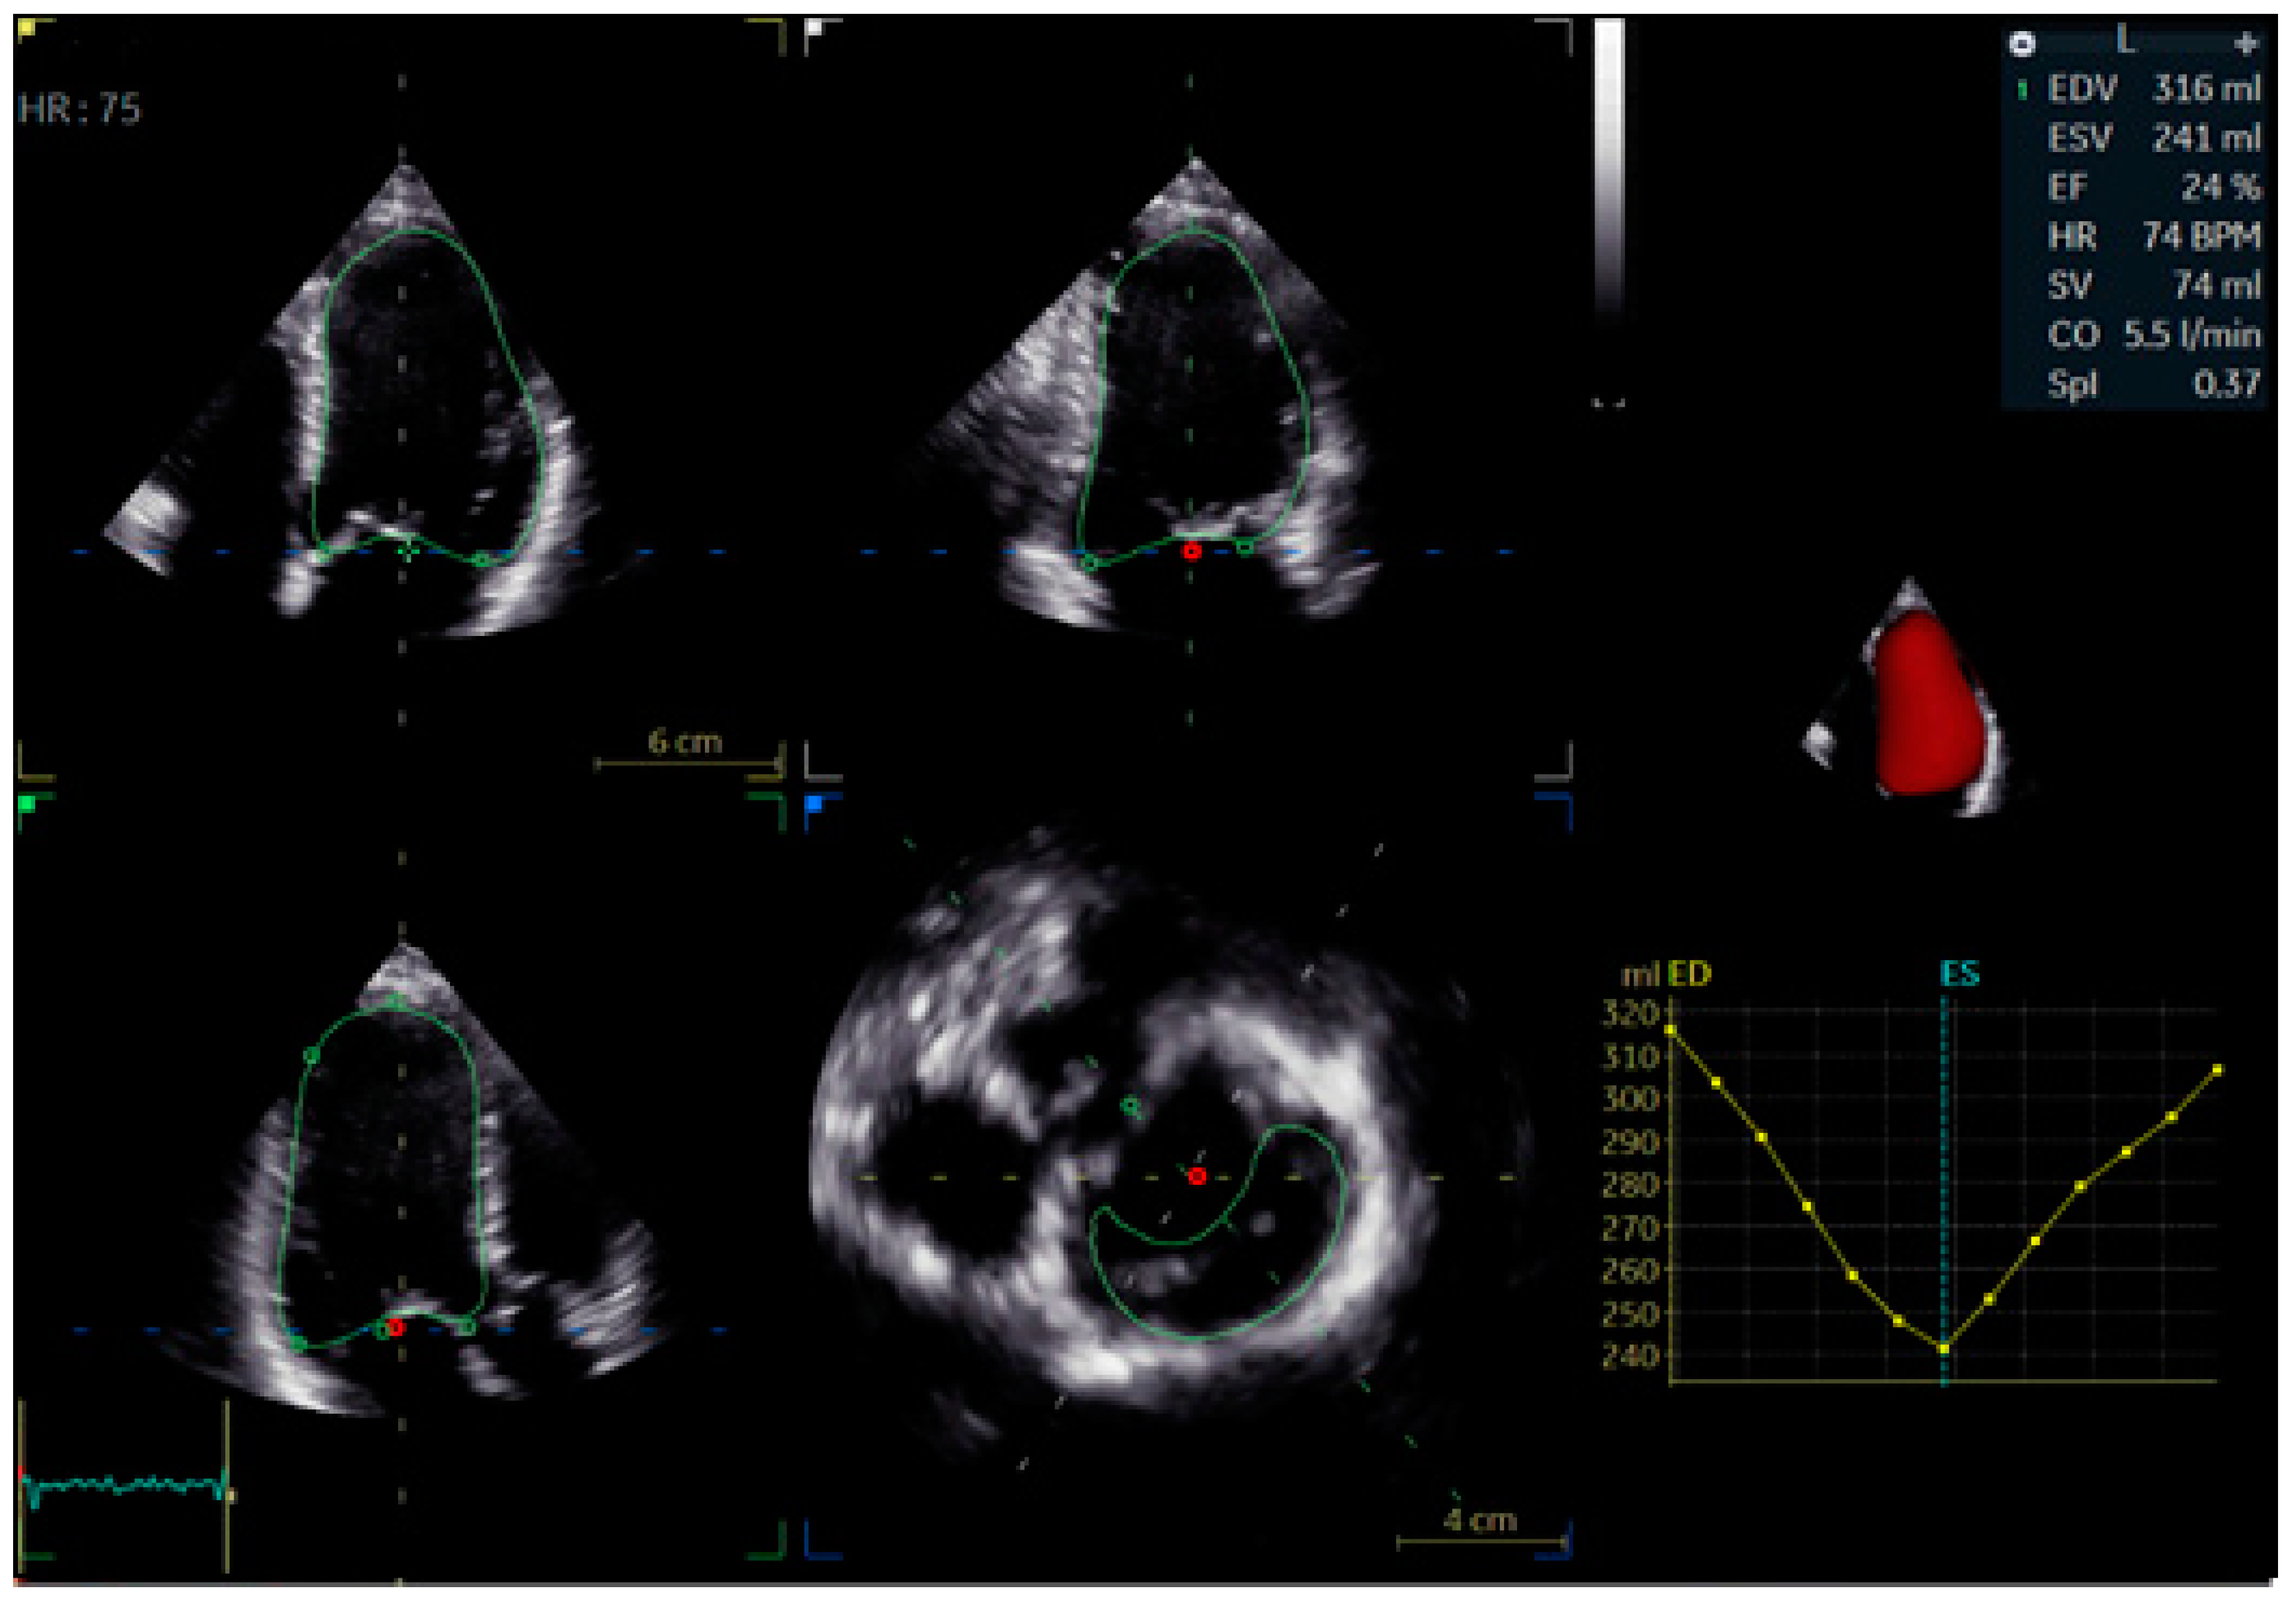

- Mei, Y.; Han, R.; Cheng, L.; Li, R.; He, Y.; Xie, J.; Wang, Z.; Wu, Y. Assessment of Cardiac Function and Ventricular Mechanical Synchronization in Left Bundle Branch Area Pacing by Speckle Tracking and Three-Dimensional Echocardiography. Am. J. Cardiol. 2023, 187, 1–9. [Google Scholar] [CrossRef]